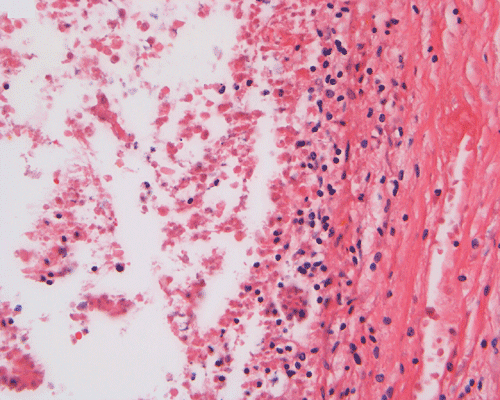

Discussion of the pathology is limited to the alimentary canal. On autopsy, the intestinal loops are largely dilated with gas accumulation. On closer examination, many small, subserosal bubbles can be seen (arrows in Panel A). The intestinal wall is also thinned out as a result of the dilatation by gas (Panel B). In the less affected areas, the intestinal  wall is not thinned out and the mucosa can still be recognized as largely intact (with autolytic changes) (Panel C and E). In the thinned out areas, the mucosa appear pink and necrotic (Panel D, F and G). The subserosal bubbles appear to be empty vesicles filled with air and they are found most frequently in the most necrotic region. In general, these features indicate widespread infarction with gas production (Panel H and I).

Coagulative and hemorrhagic necrosis is the key pathologic feature of NEC.  Necrosis is limited to the mucosa in the early stages but at least focally transmural in specimens removed from surgical resection or at autopsy.  In 10% of cases, focal necrotic pseudomembrane formation is seen.

A mixed acute and chronic inflammatory infiltrate is commonly found, limited to the mucosa in some foci but transmural in others.  Inflammation and necrosis often occur together in a given segment, but in some instances, one or the other may predominate.

Pneumatosis intestinalis, usually limited to the submucosa, is seen in 50% of surgical specimens with NEC.  The gas bubbles have been shown to contain hydrogen, a product of bacterial fermentation.  More than 50% of patients who undergo laparotomy show focal reparative epithelial changes and other evidence of healing, such as the formation of granulation tissue and crypt distortion.  Villous atrophy may also be observed.  Such reparative changes suggest that NEC evolves gradually before a catastrophic event, such as perforation, brings it to clinical attention.